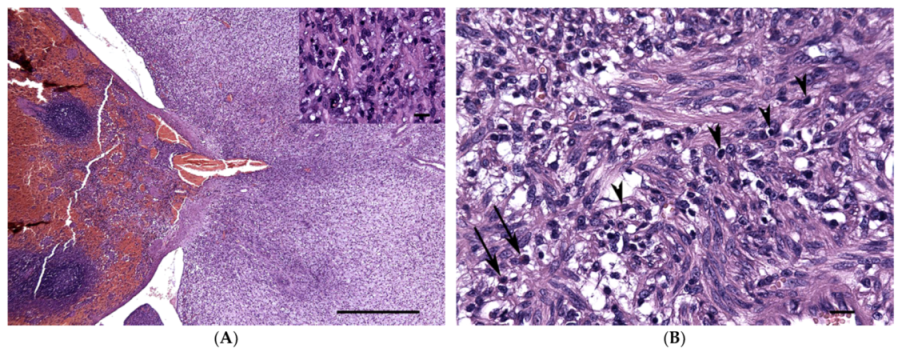

A Recurrent Inflammatory Myofibroblastic Tumor-like Lesion of the Splenic Capsule in a Kitten: Clinical, Microscopic and Ultrastructural Description

2. Case Presentation